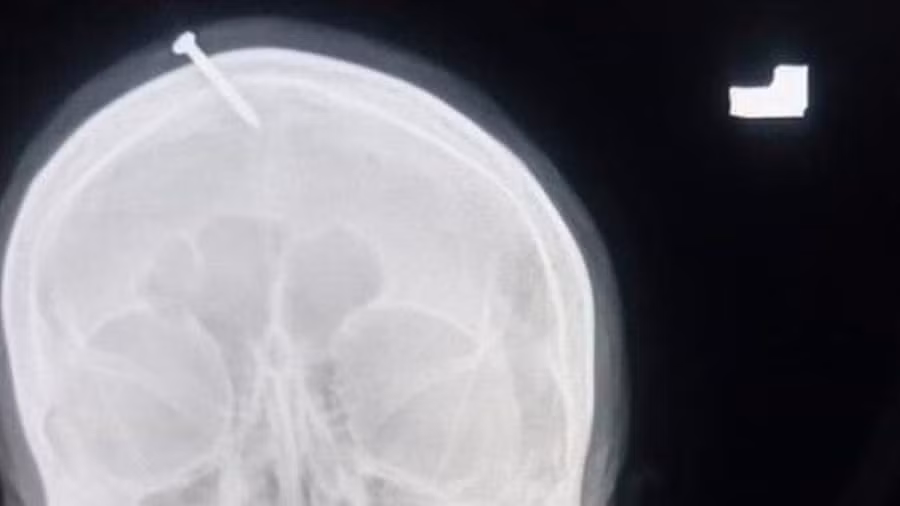

Một bức ảnh chụp X-quang đã xác nhận tuyên bố của người phụ nữ, nhưng câu chuyện của cô ấy thực sự khiến nhân viên bệnh viện không nói nên lời.

Người phụ nữ giải thích rằng chiếc đinh trong đầu mình là do một thầy lang đã hứa với cô rằng nó sẽ đảm bảo rằng cô sẽ sinh con trai chứ không phải là con gái.

Lúc đầu, người phụ nữ nói với các bác sĩ rằng thầy lang đã hướng dẫn cô hát một số câu thánh ca trong khi đóng chiếc đinh dài vào đầu, nhưng sau khi kiểm tra vết thương, các bác sĩ tin rằng cô không thể tự mình làm điều đó, phải có một người khác đóng chiếc đinh đó vào đầu cô.

Sau khi tiến hành chụp X-quang và xác nhận rằng chiếc đinh không vào não của người phụ nữ, các bác sĩ đã tìm cách lấy dị vật ra khỏi hộp sọ.